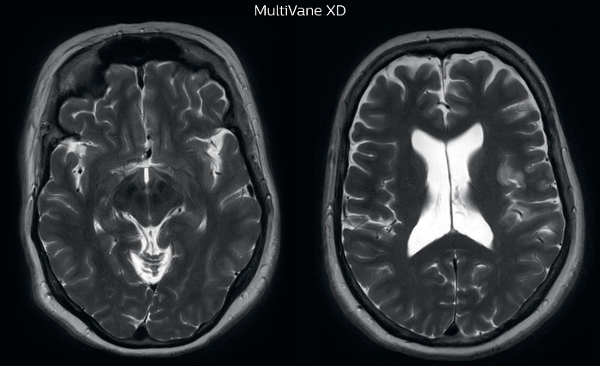

MRI motion artifact reduction in brain

The images made with MultiVane XD show significant reduction in motion artifact compared to the T2-weighted images without MultiVane below them.

Scanned on Ingenia 3.0T

Trevor Andrews, PhD, explains that the team compared motion artifacts seen in the brain with MultiVane XD and with T2-weighted TSE. “In nine out of the ten datasets in our studywe saw clear improvementswith MultiVane XD, while in the tenth dataset image qualitywas comparable. The MultiVane XD sequence is now used in the majority of patients that present at UVM for brain MRI.”

“We saw MultiVane XD provide remarkable improvement, not only for artifacts caused by patient motion, but also for the extent of pulsation artifacts in the basal cisterns. Based on these results, we have added the MultiVane XD sequence to our brain studies,” says Dr. Nickerson.

“MultiVane XD is especially useful when imaging patients with diseases that cause white matter changes on T2-weighted images, such as MS, small vessel disease, vasculitis and sarcoidosis,” says Dr. Nickerson. “Many of these are only visible on T2-weighted or FLAIR images, and sometimes aren’t even seen with FLAIR images. However, when using MultiVane XD and we don’t see any motion on the rest of the scan, but still do see a signal abnormality, we can probably attribute that to a real disease process, rather than an artifact.”